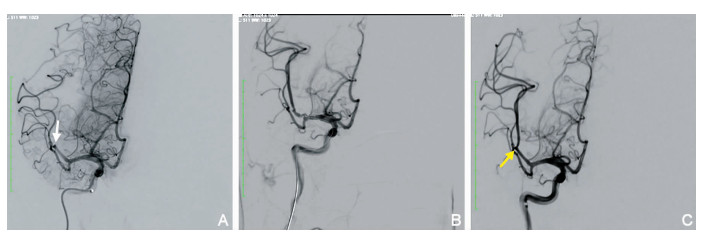

Therapeutic effect analysis of mechanical thrombectomy for acute middle cerebral artery M2 segment occlusion

ZHU Yu-you, WANG Li, LIU Tian-long, ZHANG Chao, SONG Jian-long, WANG Peng, SUN Wen, HU Wei, WANG Guo-ping

2021, 19(10): 1633-1636,1649. doi: 10.16766/j.cnki.issn.1674-4152.002129

868 8

Abstract:

Objective  To explore the efficacy and safety of mechanical thrombectomy for acute occlusion of the M2 segment of the middle cerebral artery.  Methods  Twenty patients with acute cerebral infarction who were subjected to mechanical thrombectomy for M2 segment middle cerebral artery occlusion in the First Affiliated Hospital of the University of Science and Technology of China from September 2019 to October 2020 were retrospectively collected. Amongst them, 8 were males, and 12 were females. Their ages ranged from 32 to 84 (62.5±14.4) years. The National Institutes of Health Stroke Scale score was (14±3) on admission. The preoperative ASPECTS score was 8.0 (7.0, 9.0) points. The aetiology classification adopted was TOAST classification, including 2 cases of aortic atherosclerosis, 10 cases of cardiogenic embolism, 5 cases of other causes, 3 cases of unknown cause. Before mechanical thrombectomy, intravenous thrombolysis was performed in 6 cases, of which 5 cases were treated with recombinant tissue plasminogen activator and 1 case with urokinase. There were 14 patients with dominant M2. The operation mode, recanalization and intracranial hemorrhage were analyzed, and the prognosis 90 days after operation was analyzed. An mTICI grade 2b-3 indicated successful recanalisation of blood vessels, and an mRS score of 0-2 meant good clinical prognosis.  Results  The average time from onset to femoral artery puncture in 20 patients was 200-582 min, the median time was 370 (277, 483) min, and the time from onset to recanalisation was (481.3±121.4) min. Stents were only used in 6 patients to remove the thrombus, direct aspiration was only used in 8 patients to remove the embolus, and stent combined with aspiration technology was used in 6 patients to remove the embolus. The number of emboli removed was 2 (1, 2). The successful recanalisation rate was 95%. Four patients had intracranial haemorrhage, and two of them had symptomatic intracranial haemorrhage. At 90-day follow-up, 1 patient died, the good prognosis rate was 65%. Univariate analysis showed that combined intravenous thrombolysis, without sICH were associated with good 90-day prognosis.  Conclusion  Mechanical thrombectomy for acute ischemic stroke patients with middle cerebral artery M2 occlusion is safe and effective. Combined intravenous thrombolysis, without sICH are associated with good prognosis at 90 days.